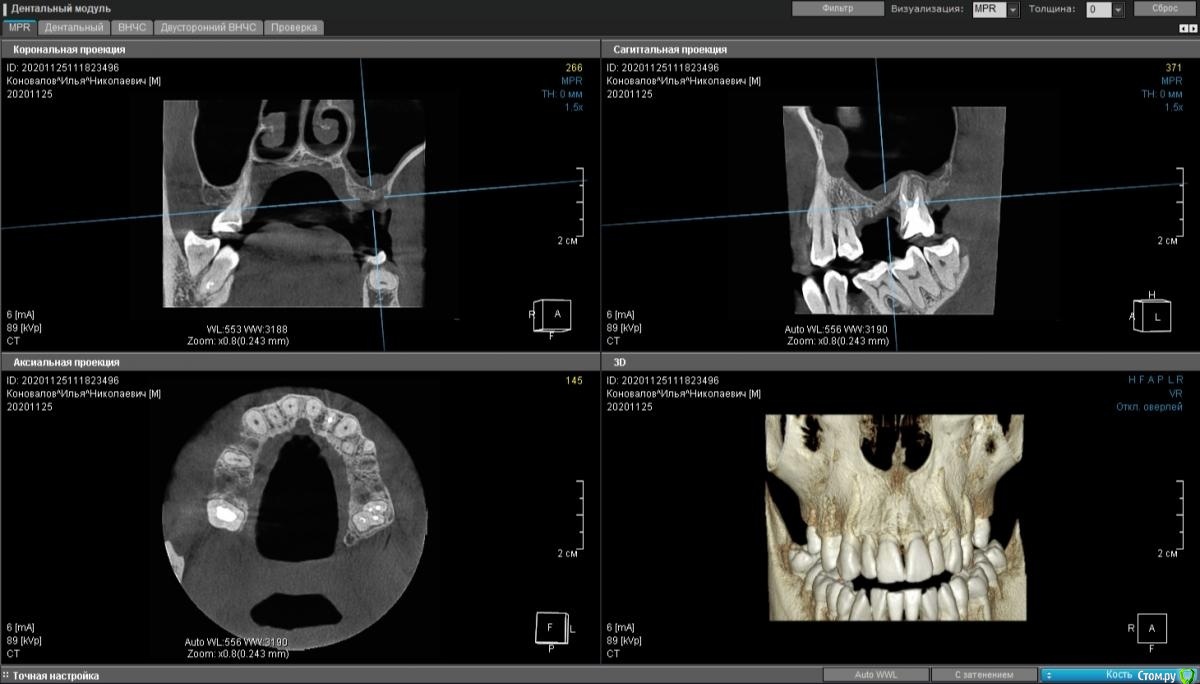

moises Опубликовано 30 ноября, 2020 Поделиться Опубликовано 30 ноября, 2020 Добрый день,коллеги.3 месяца назад удалены 25,26.Планируется установка 2х имплантатов .Если в области 15 можно было пойти с закрытым синуслифтингом, то в области 16 кости 3мм.Нужна помощь в тактике лечения.?Идти на ОСЛ в области 2х зубов и отсроченно имплантаты ? И можно ли с такой утолщенной слизистой его производить?Спасибо!P.S.Закрытые синусы делаю,открытые -делал только на фантомах и препаратах. Ссылка на комментарий

kramer Опубликовано 30 ноября, 2020 Поделиться Опубликовано 30 ноября, 2020 Проверить по кт, что там с соустьем, сделать ОСЛ с одномоментной имплантацией 1 Ссылка на комментарий

Александр07 Опубликовано 26 декабря, 2020 Поделиться Опубликовано 26 декабря, 2020 коллеги простите за офтопа если соустье плохо проходимо или обтурировано или не прослеживается, но жалоб на заложенность или явления гайморита нет и по снимку нет воспалений, что делаете, какая подготовка к операции, какие рекомендации?что искать на КТ как смотрите соустье, на что обращать внимание?Соустье на кт видно обычно хорошо в верхнем отделе пазухи, если закрыто или ещё что или к Лору или назначить назонекс на месяц например и затем повторить кт, но если утолщение не большое и вся пазуха чистая то с соустье скорее всего все в порядке 1 Ссылка на комментарий